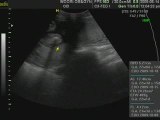

richjoy baby-19 weeks old